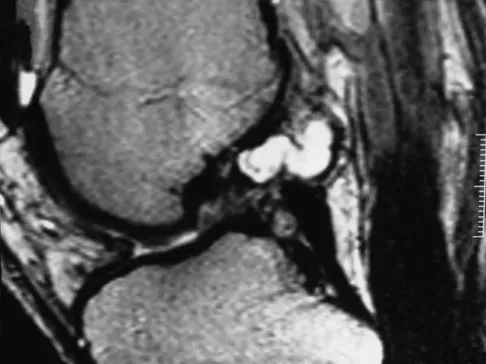

A 35-year-old woman who is a recreational runner reports posterior knee pain and tightness in the knee with flexion during running. She denies any history of trauma. Examination reveals normal patellar glide and tilt and no patellar apprehension. Range of motion is 5 degrees to 120 degrees, and quadriceps function and knee ligamentous examination are normal. Radiographs are normal. An MRI scan is shown in Figure 18. What is the most likely diagnosis?

Explanation

Figures 36a and 36b show the MRI scans of a 15-year-old girl who has had pain and recurrent hemarthrosis in the knee for the past year. Plain radiographs are normal. What is the most likely diagnosis?

Explanation